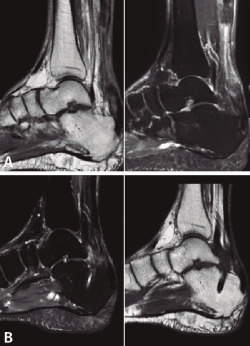

A todos los pacientes se les realizó una radiografía simple, sin detectar ninguna lesión ósea, y una resonancia magnética (RM) preoperatoria para demostrar la existencia de una rotura completa del TC, poder medir el defecto existente y evaluar el estado del FHL previo a la transferencia, y las posibles variantes anatómicas que puedan facilitar o dificultar la técnica quirúrgica descrita. Finalmente, se realizó una RM postoperatoria a todos los pacientes, a los 9-12 meses después de la cirugía, para ver la correcta integración del FHL en el calcáneo y la posible reparación del TC.

La RM preoperatoria mostró una rotura completa del TC y la retracción proximal del tendón en todos los casos, con un defecto medio de 75 mm (mediana: 76; rango: 65-85 mm). No se observó patología del tendón de FHL u otras anormalidades en ninguno de los pacientes.

Posteriormente, a todos pacientes se les realizó una RM postoperatoria a los 9-12 meses, para observar la correcta integración de la plastia en el túnel del calcáneo. En todos los casos se objetivó la reparación del defecto del TC, lo cual lo atribuimos a la aposición del vientre muscular del FHL y a la carga en ausencia de estrés mecánico (Figura 5).

Figura 5. Imagen de resonancia magnética (RM) preoperatoria (A) y RM a las 16 semanas postoperatorias (B), donde se observa la correcta integración de la plastia en el túnel del calcáneo y la reparación e hipertrofia del tendón calcáneo.